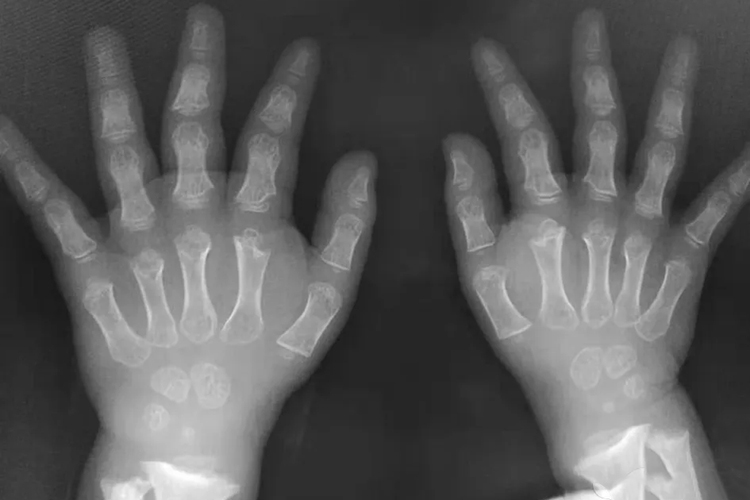

软骨发育不良的婴儿,临床表现为身材矮小(低于同龄标准身高4-5个标准差,四肢短小,躯干发育正常,导致四肢与躯干不成正常比例,且肢体远端受累轻于近端)、头颅较大、前额突出、鼻背塌陷、下颌相对突出。环指与中指不能正常并拢,呈三叉状,称为三叉戟手,部分患儿出现桡骨头脱位或肘关节屈曲挛缩等表现,下肢较正常更短且弯曲成弓形,可见肌肉明显臃肿;腰椎前凸、臀部后翘、膝内翻或膝外翻。